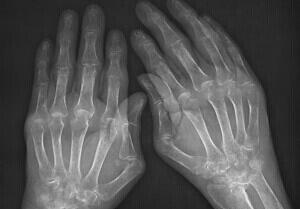

(图:体查、X线片检查都显示高女士类风湿病情严重)